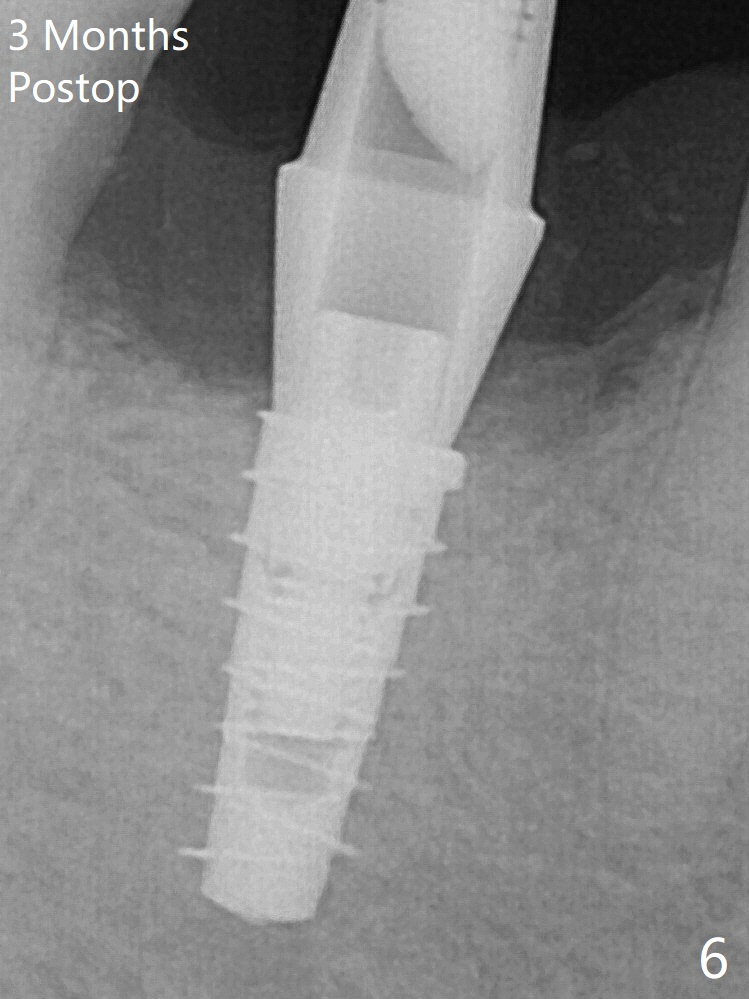

For safety, a 4x9 mm IBS implant is placed with insertion torque 40 Ncm; a 5x5.7(4) mm abutment is immediately placed for an immediate provisional to cover the large socket and keep Vera graft in place (Fig.4 *). Yellow dashed line: apical osteotomy; red dashed line: Mental Loop. Impression is taken nearly 3 months postop (Fig.6). The bone density around the implant increases 7 months post cementation (Fig.8 *). The higher density bone seems to extend coronally 1 year 7 months post cementation (Fig.9).